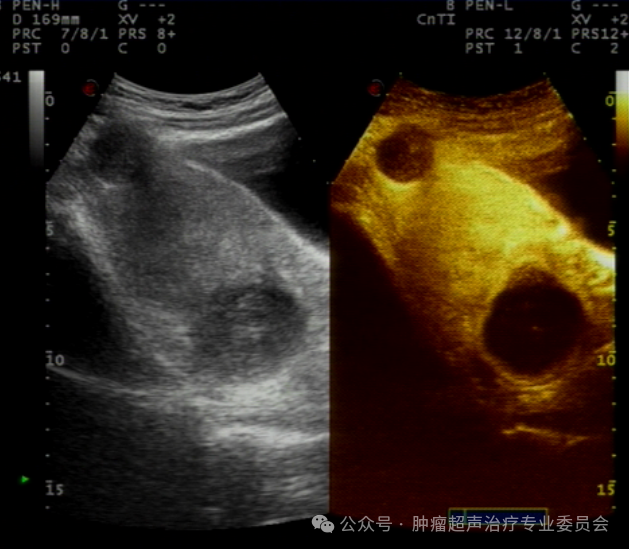

治疗后半年复查

子宫后壁肌瘤缩小至29*25mm,子宫前壁肌瘤

缩小至26*20mm。较治疗前缩小达40%。